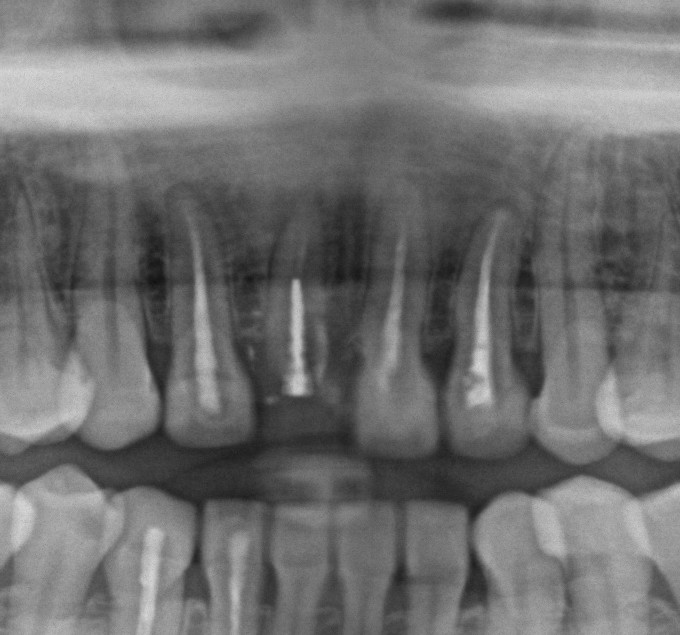

DB181311_161028164327(調整後)落ち着いたらエンドします。このようなケースは根尖が大きく開いてること多いので、ポイント至適はマスト

DB181311_161028165002(調整後)シーラーが出てます

DB181311_161128160106(調整後)ばっちり骨も治りましたね。